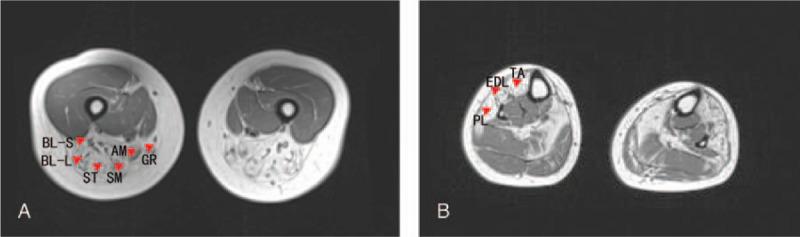

We describe the case of a 32-year-old woman with GNE myopathy. The patient presented with progressive weakness of the lower-limb muscles that had spread to her legs. Her serum creatine kinase level was higher than the normal range. Mild myogenic changes were detected in the tibialis anterior muscles on electromyography, and moderate fatty infiltration was observed in various lower-limb muscles on magnetic resonance imaging. Histopathological examination of a skeletal muscle biopsy specimen revealed variation in muscle fiber size, rimmed vacuoles, and disorganized intermyofibrillar networks. DNA sequencing testing revealed a compound heterozygous mutation consisting of a known mutation (c.620A > T in exon 3) and a novel (exon 1 deletion) mutation.

我们描述了一名32岁GNE肌病女性患者的病例。患者表现为下肢肌肉进行性无力,并已蔓延至腿部。她的血清肌酸激酶水平高于正常范围。肌电图检查发现胫前肌有轻度肌源性改变,磁共振成像观察到下肢各肌肉有中度脂肪浸润。骨骼肌活检标本的组织病理学检查显示肌纤维大小不一、边缘空泡和肌原纤维间网络紊乱。DNA测序检测发现一个复合杂合突变,由一个已知突变(外显子3中的c.620A>T)和一个新的(外显子1缺失)突变组成。